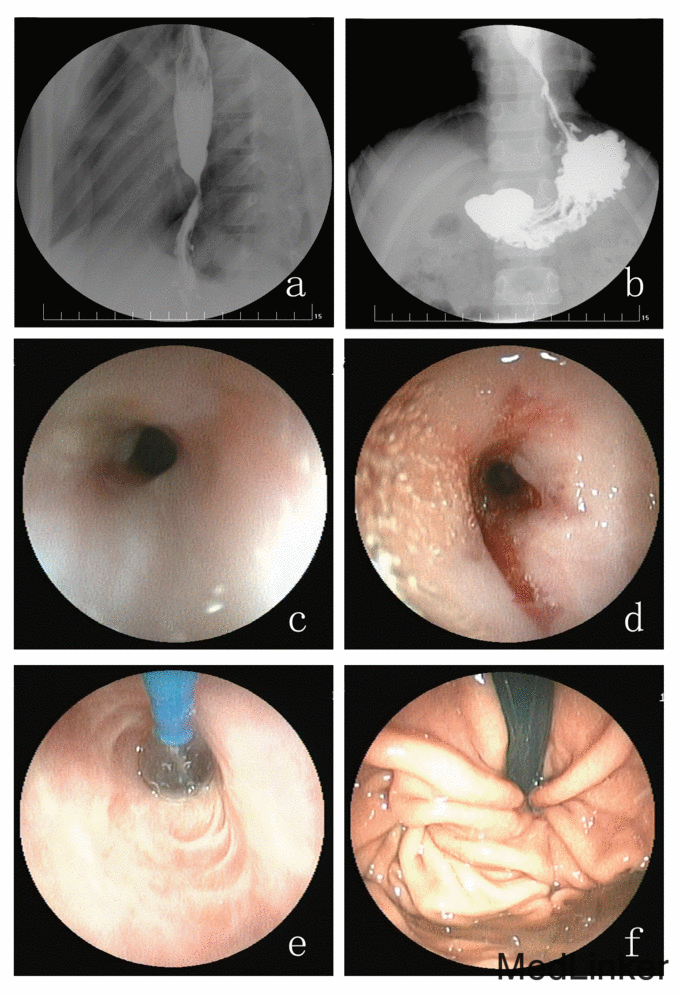

诊断:GERD,反流性食管炎(LA-D级),消化性食管狭窄,食管裂孔疝 确诊后根据患儿病情行食管裂孔疝修补术(采用C-PHR-7X10-U型COOK软组织修补片)加Toupet腹腔镜下胃底折叠术。术后患者症状明显缓解,切口愈合后出院。出院半个月后因吞咽困难症状再次出现二次入院。上消化道造影示:食管下段管腔狭窄,管壁尚光滑;胃底折叠术后改变(图2a、2b)。纤维胃镜检查示:食管下段管腔四壁可见多条瘢痕形成,距门齿29 cm食管明显狭窄(图2c),行内镜下球囊扩张术,导丝引导下球囊(直径10 mm)扩张,共3次,局部见少量渗血,无撕裂、穿孔(图2d)。术后患儿吞咽困难症状改善,进食半流质饮食无困难。3周后为再次扩张治疗,第三次入院,复查纤维胃镜示:食管下段管腔四壁可见多条瘢痕形成,距门齿29 cm食管明显狭窄,给予导丝引导下球囊逐级扩张至直径12 mm,共3次(图2e),扩张后进镜观察胃底呈折叠术后改变(图2f)。